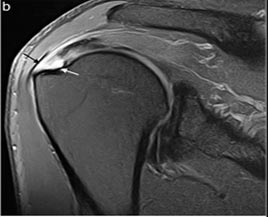

Lesões do Tendão do Supraespinhal.

Lesão Supraespinhal

Tendão Reparado Após Artroscopia de Ombro